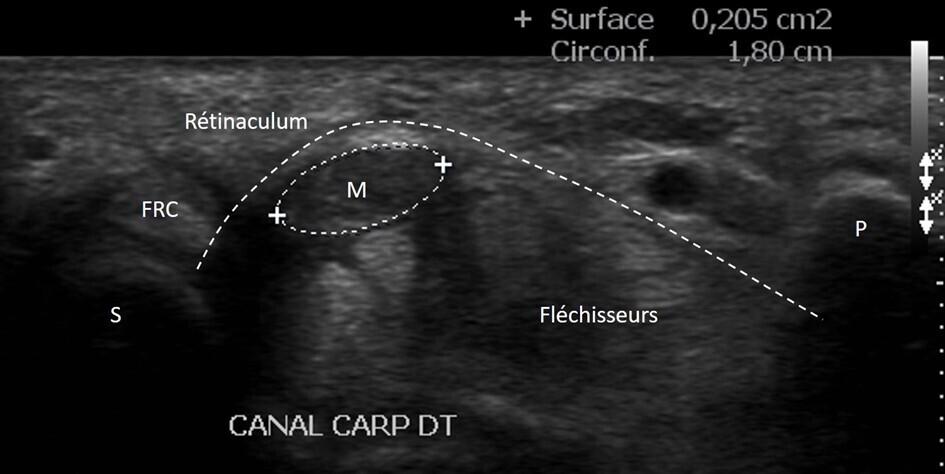

Syndrome du canal carpien

Une autre application de l’échographie en rhumatologie concerne le diagnostic du syndrome du canal carpien. Elle permet de visualiser directement l’épaississement du nerf médian via l’augmentation de sa surface (fig. 3). La surface transversale du nerf médian doit être mesurée au site de son plus grand élargissement, et l’évaluation doit être faite du milieu de l’avant-bras jusqu’à la paume. La présence d’éventuelles anomalies anatomiques causales, comme des kystes ou des hypertrophies des tendons fléchisseurs, peut être recherchée mais est rarement observée.

L’échographie ne remplace pas l’électromyogramme (EMG) et apporte plutôt des renseignements complémentaires. Un consensus d’experts a récemment recommandé d’associer l’échographie à l’EMG car la combinaison de ces deux examens est plus informative que leur utilisation isolée. L’échographie est particulièrement utile dans les cas où les résultats de l’EMG sont atypiques, normaux, ou en cas de récidive après chirurgie.4